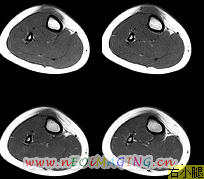

标题: PED0931:男,5岁,发现双小腿软组织肿块1年,质地中等,无 [打印本页]

标题: PED0931:男,5岁,发现双小腿软组织肿块1年,质地中等,无

多发性神经纤维瘤?

考虑多发性神经纤维瘤.

考虑多发性神经纤维瘤.支持

多发性神经纤维瘤可能。

支持:多发性神经纤维瘤。